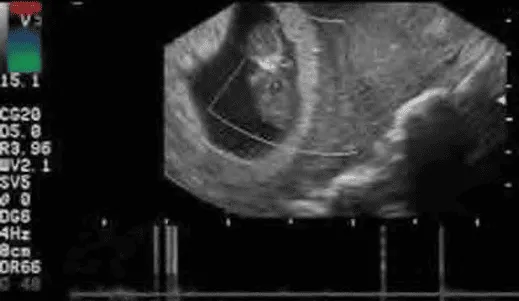

- Trứng trống (blighted ovum): Chỉ sự hiện diện của túi thai nhưng không thấy phôi thai bên trong.

- Thai ngưng phát triển sớm: Chỉ hình ảnh túi thai có phôi nhưng không có hoạt động tim thai.

Phần tiêu đề “Thai lưu”Siêu âm xác nhận khi đáp ứng ≥ 1 tiêu chí sau:

- CRL ≥ 7 mm không thấy tim thai.

- MSD ≥ 25 mm không thấy phôi thai.